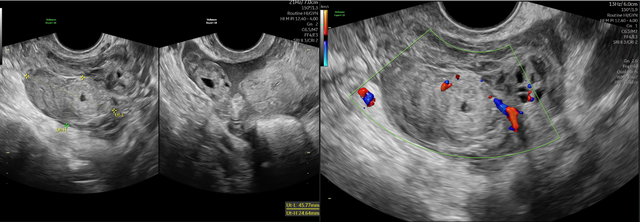

Hình ảnh siêu âm tử cung phần phụ

Tuy nhiên, khi thăm khám, BS ghi nhận túi cùng căng, nghi ngờ có dịch trong ổ bụng. Siêu âm đầu dò phát hiện khối giống túi thai nằm tại vòi trứng trái kèm dịch máu trong ổ bụng. Định lượng beta-hCG cho kết quả 289 mIU/ml. "Bệnh nhân may mắn được phát hiện trước khi diễn tiến nặng hơn", BS Vũ cho hay.